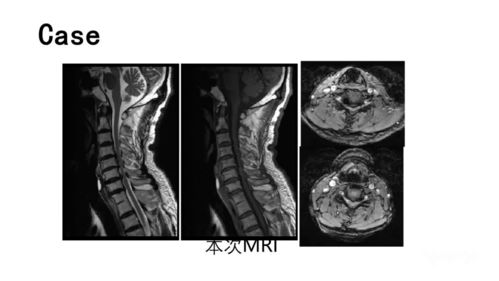

- MRI(磁共振成像): 是诊断神经根型颈椎病的首选影像学方法,它可以清晰地显示椎间盘突出、神经根袖(硬膜囊)受压、神经根水肿以及软组织(如韧带)的病变,T2加权和STIR(短时反转恢复)序列对于显示神经根受压和水肿非常敏感。